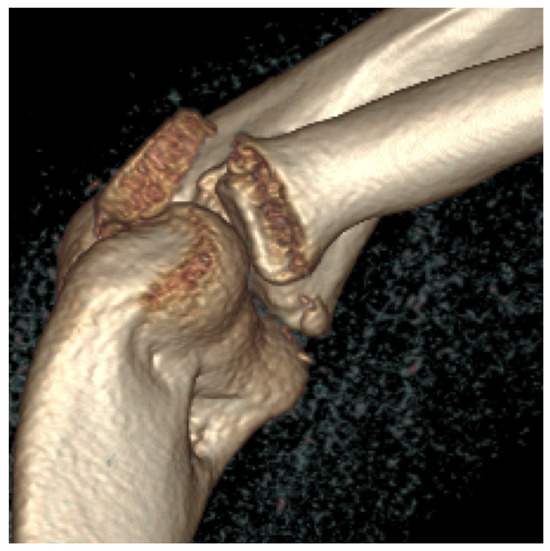

We investigated whether interrater reliabilities of the AO/OTA classification of patellar fracture change with the imaging modalities applied, including plain radiography and two- and three-dimensional (2-D and 3-D) computed tomography (CT). Seven orthopedic specialists and four orthopedic residents completed a survey of 50 [...] Read more.

We investigated whether interrater reliabilities of the AO/OTA classification of patellar fracture change with the imaging modalities applied, including plain radiography and two- and three-dimensional (2-D and 3-D) computed tomography (CT). Seven orthopedic specialists and four orthopedic residents completed a survey of 50 patellar fractures to classify the fractures according to the AO/OTA classification for patellar fractures. Initially, the survey was conducted using plain radiography only, then with 2-D CT introduced three weeks later and 3-D CT introduced six weeks later. Fleiss’ Kappa coefficients were calculated to determine interrater reliability. The overall interrater reliability of the AO/OTA classifications was 0.40 (95% CI, 0.38–0.42) with plain radiography only and 0.43 (95% CI, 0.41–0.45) with the addition of 2-D CT. With the addition of 3-D CT, the reliability was significantly improved to 0.54 (95% CI, 0.52–0.56). In specialists, interrater reliability of the classifications was moderate with all three imaging modalities. With the use of 3-D CT, interrater reliability of the classification was 0.53 (95% CI, 0.50–0.56), which was significantly higher than that with the use of 2-D CT (κ = 0.45; 95% CI, 0.42–0.48). In residents, interrater reliability of the classification was 0.30 (95% CI, 0.24–0.36) with plain radiography. The reliability improved to 0.49 (95% CI, 0.43–0.56) with the addition of 2-D CT, which was significantly higher than that with plain radiography only. The use of 3-D CT imaging improved interrater reliability of the classification. Therefore, surgeons, especially residents, may benefit from using 3-D CT imaging for classifying and planning the treatment of patellar fractures. Full article

Show Figures

Figure 1